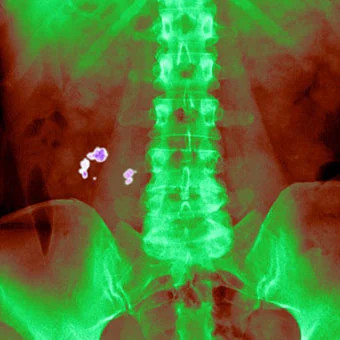

Batu ginjal

Batu ginjal terbentuk akibat penumpukan mineral dan garam dalam urine yang pekat. Saat tubuh kekurangan cairan, volume urine menurun dan menjadi lebih terkonsentrasi, sehingga memudahkan mineral mengkristal dan membentuk batu ginjal.

Kondisi ini dapat menimbulkan nyeri hebat, terutama saat batu bergerak di saluran kemih, serta menimbulkan gangguan buang air kecil.